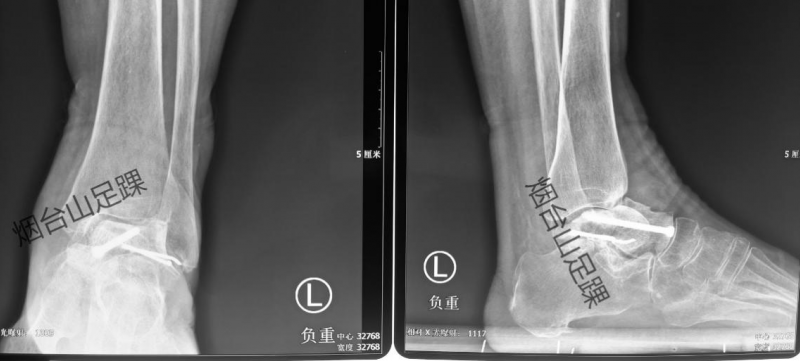

术前影像显示,患者的距骨坏死塌陷。

术后X线片显示,胫距关节匹配良好。